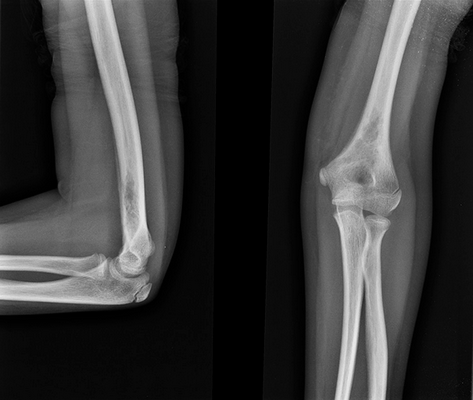

Использование различных методов визуализации (рентгенография, КТ, МРТ) позволяет выявить очаги деструкции величиной до 5 см с четкими границами без склеротических изменений, иногда — патологические переломы, уплощение пораженных позвонков (vertebra plana).